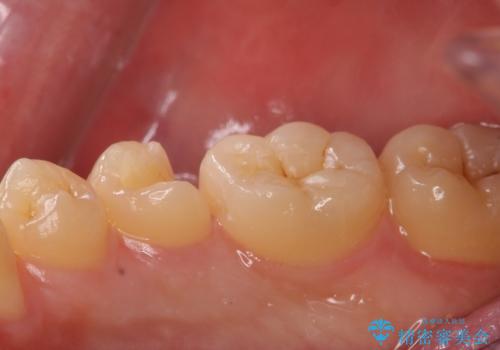

歯と歯の間に虫歯(コンタクトカリエス)がありましたので、拡大鏡下で虫歯を取り、白い詰め物(e-maxインレー)で治療を行いました。